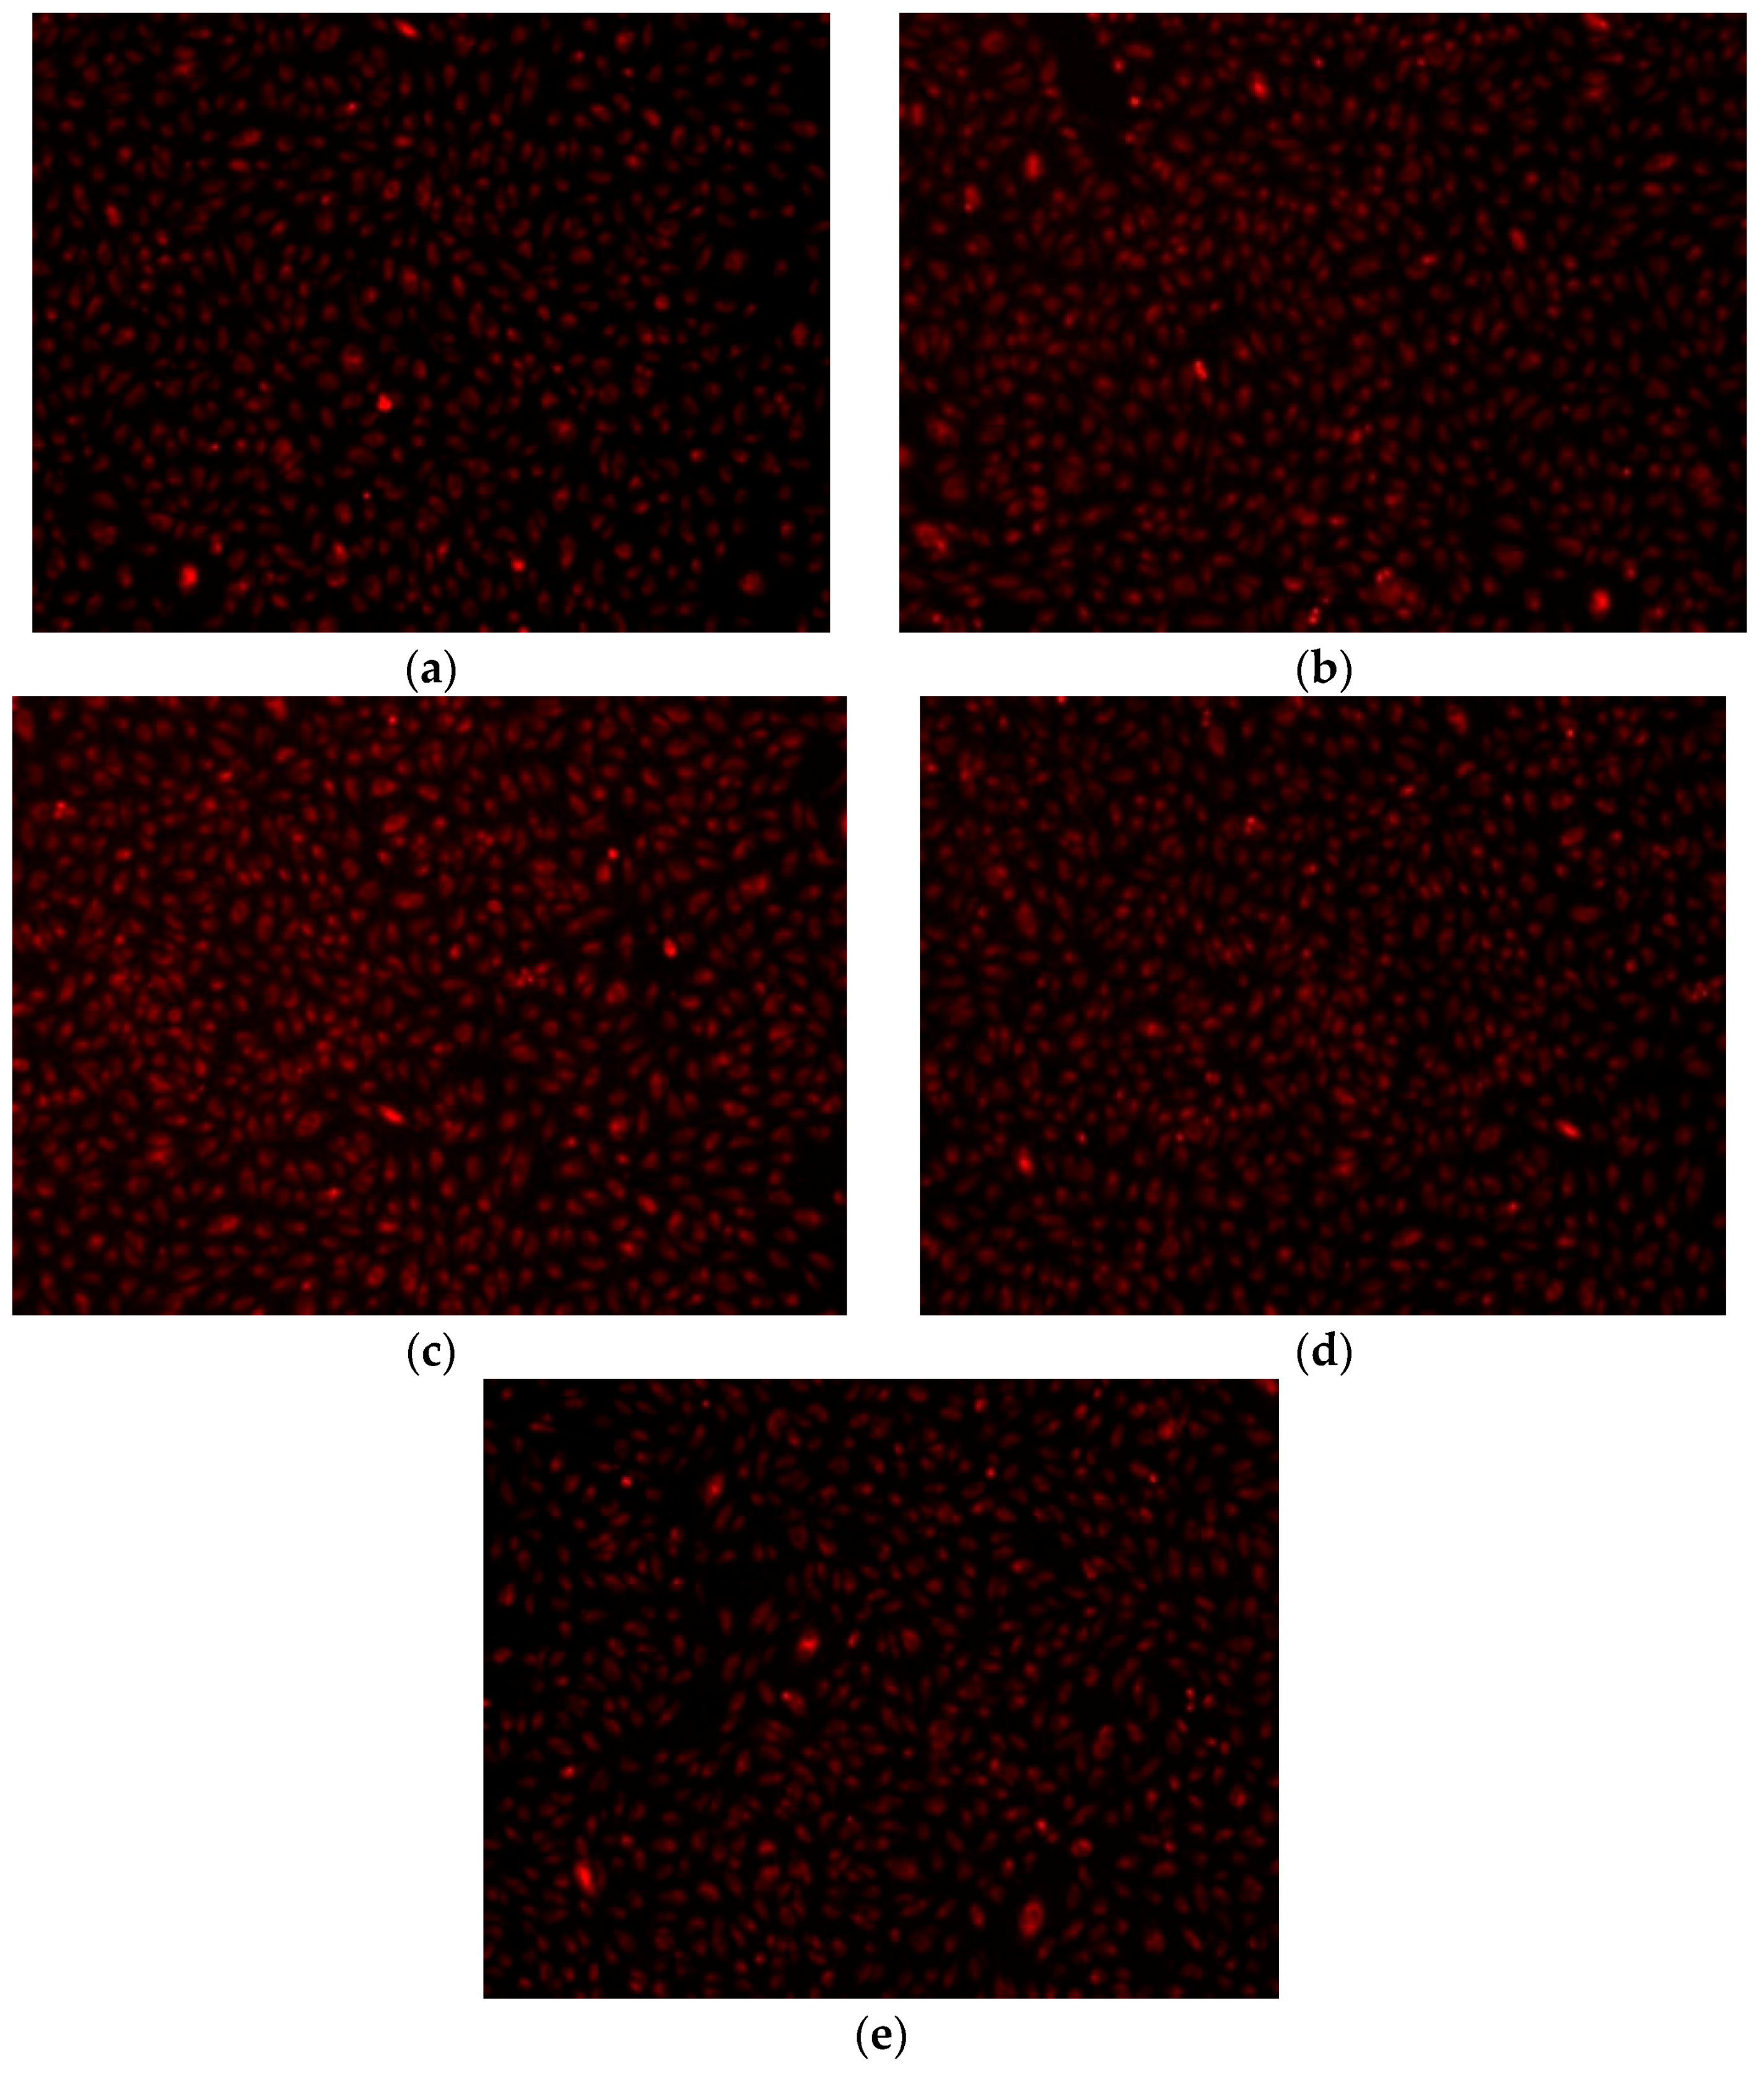

- Fluorescent microscopy for tracing of living cells